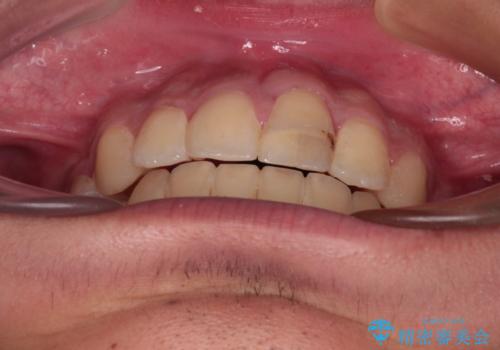

膨らんだ口元 ワイヤー装置での抜歯矯正

- 口元の突出感を気にして来院された患者様です。

上下前歯が著しく前突している状態であったので、上下左右の第1小臼歯4本を抜歯し、ワイヤー装置にて矯正治療を行うこととしました。

舌の突出癖により、前突になったと考えられたため、舌のトレーニングをしっかりと行うよう指導しました。